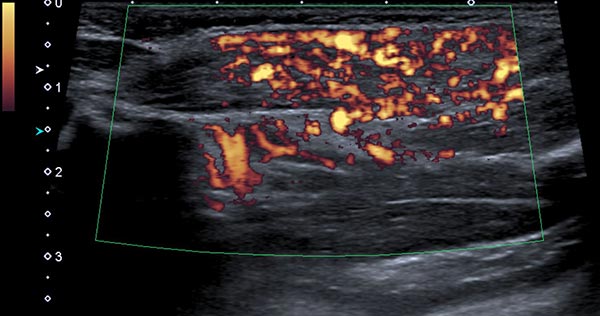

Power Doppler imaging shows strong perfusion of the mass, so that a vascular tumor is assumed. The strong blood flow is shown here in orange in the B-scan, while the direction of flow is not color-coded.

Power Doppler imaging at the end of the 8th month of life shows not only an increase in volume of the subcutaneous tumor, but also a further marked increase in perfusion (color-coded in orange).